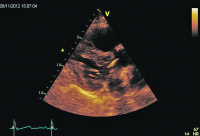

Rechtsventrikulärer Einflusstrakt

Abbildung 2: Parasternale Darstellung des rechtsventrikulären Einflusstraktes. Flottierender Thrombus (Pfeil) im RA. Dilatierter und hypokontraktiler RV. RA: rechter Vorhof; RV: rechter Ventrikel; TV: Trikuspidalklappe.